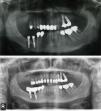

Material y métodosSe trata de un estudio descriptivo retrospectivo que presenta una serie de 11 casos clínicos de PIA diagnosticados y tratados en el ámbito del Hospital de La Princesa (Madrid) y la Clínica Universidad de Navarra (Pamplona). Se han incluido todos los casos con implantes integrados clínica y radiológicamente y con imágenes radiolúcidas a nivel de los ápices de los implantes entre 2002 y 2013: 4 pacientes eran asintomáticos (no se han intervenido salvo una endodoncia del diente vecino en un caso) y 7 pacientes sintomáticos. Los pacientes sintomáticos se trataron con abordaje estándar de «apicectomía» mediante una incisión a nivel del vestíbulo oral, practicándose legrado del tejido de granulación y en 3 de ellos la resección del ápice implantario para facilitar el acceso a la cavidad y eliminar la zona más contaminada del implante (fig. 1a,b,c). No se ha realizado la detoxificación de la superficie implantaria. Se efectuó relleno óseo (asociado con uso de membranas de colágeno reabsorbibles) en 3 casos: con autoinjerto de hueso alveolar particulado en 2 casos y con hueso artificial de origen bovino en el caso restante (fig. 1d). En un caso se realizó además tratamiento endodóncico de un diente vecino por vitalidad pulpar negativa (tabla 1).

a) Abordaje tipo «apicectomía» mediante una incisión a nivel del vestíbulo oral. b) Exposición de la zona de osteítis periimplantaria y sección de la parte apical implantaria para facilitar el acceso. c) Zona apical del implante resecada y el tejido de granulación cureteado. d) Relleno óseo (en este caso con hueso artificial).